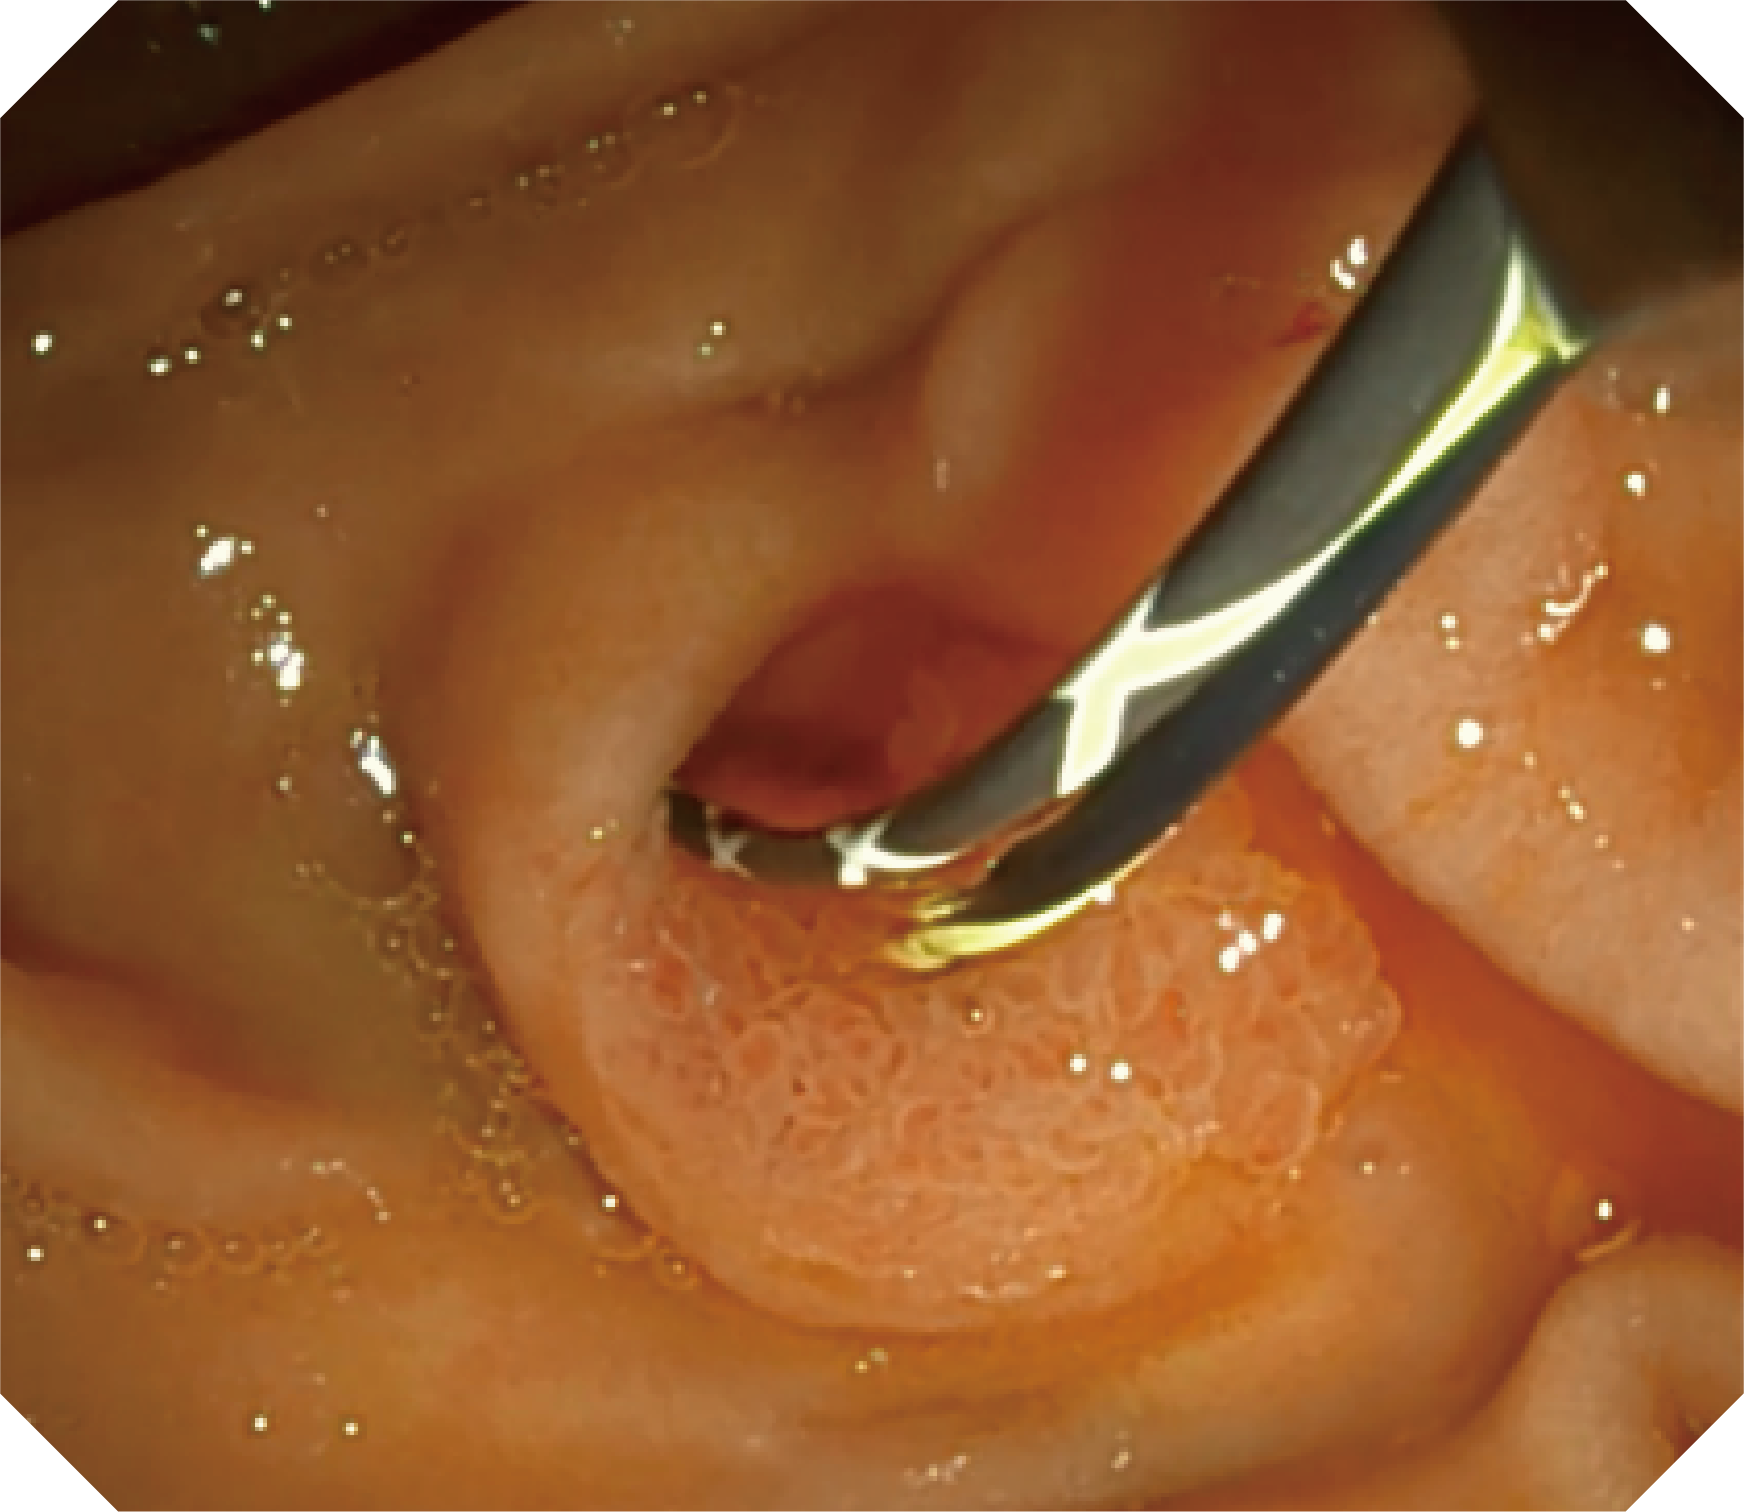

CMOS傳感器提供高清內(nèi)鏡視野 SFI/VIST光學(xué)染色技術(shù)凸顯病變區(qū)域

可拆卸先端帽

優(yōu)異的手術(shù)器械抬舉性